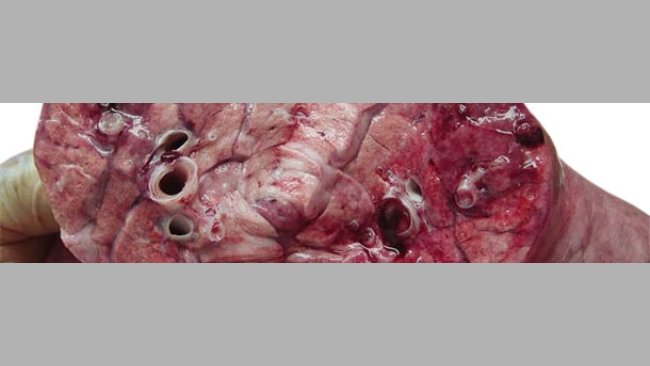

Cas clinique: Pneumonie nécrotique chez des porcelets allaitants

Dans un élevage de multiplication au Mexique, on observe une augmentation de la mortalité en maternité coincidant avec une augmentation de la température et de l'humidité ambiantes.